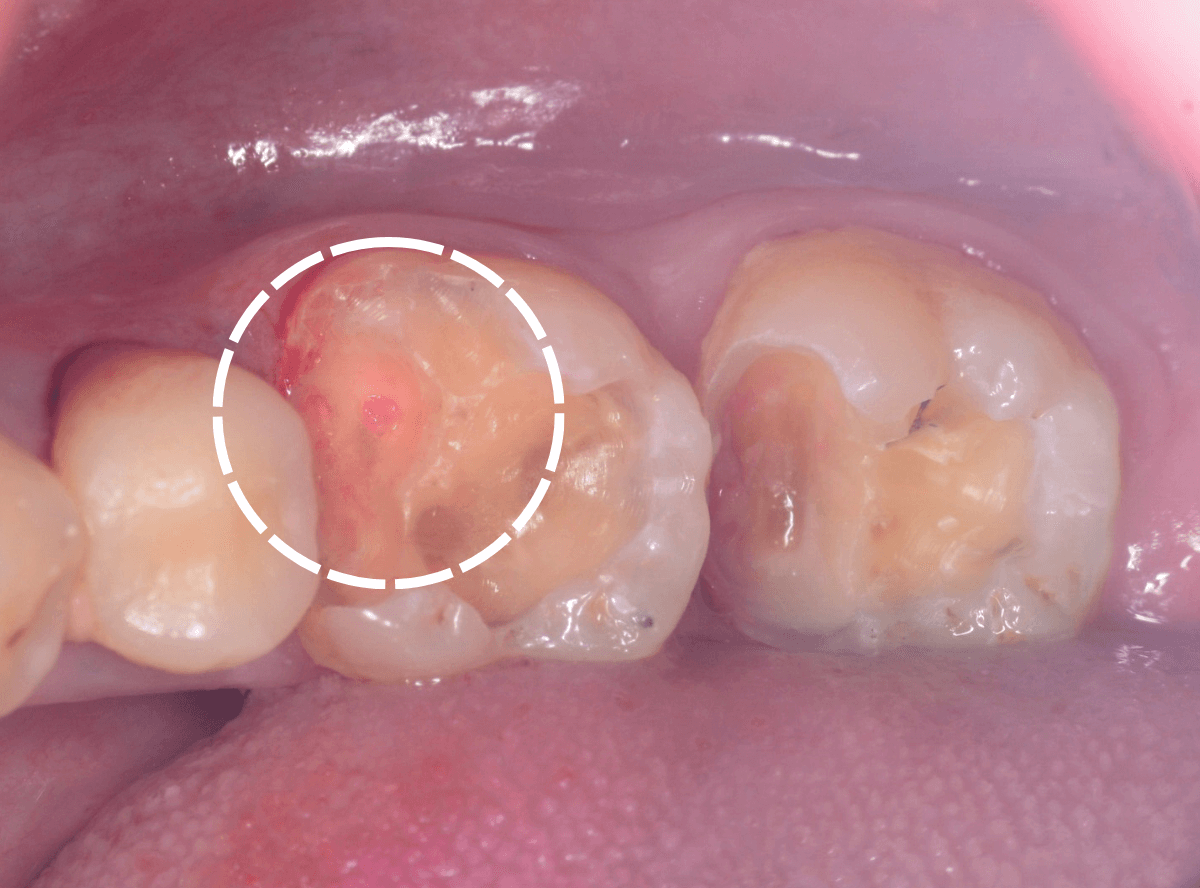

Case.14 インレーの下の歯肉まで広がった虫歯

「下の奥歯が噛むと痛む」という症状で来院された患者さんのケースです。

お口の中の状態を確認すると、奥歯の端に穴が開いているのが見えます。

ここかな?

中のお薬も慎重に外して虫歯を除去します。

虫歯が深く、歯肉の下まで浸食していましたので、歯肉を部分切除し、虫歯を全て除去したところで、奇跡的に神経スレスレの状態でとどまっていました。

何とも言えませんが、神経を残せる可能性が出てきました。

虫歯が神経まで達していなくても、治療前から自発痛(何もしなくても痛い)があれば、神経をとらなければいけません。

今回は、そこまでの症状がありませんでしたので、患者さんと相談の上、神経を取らずに残す方法で様子を見る事になりました。

痛みが出ませんように。。。